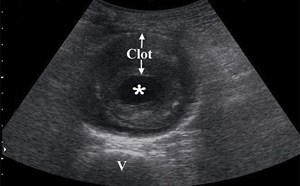

Deep Vein Thrombosis (DVT)